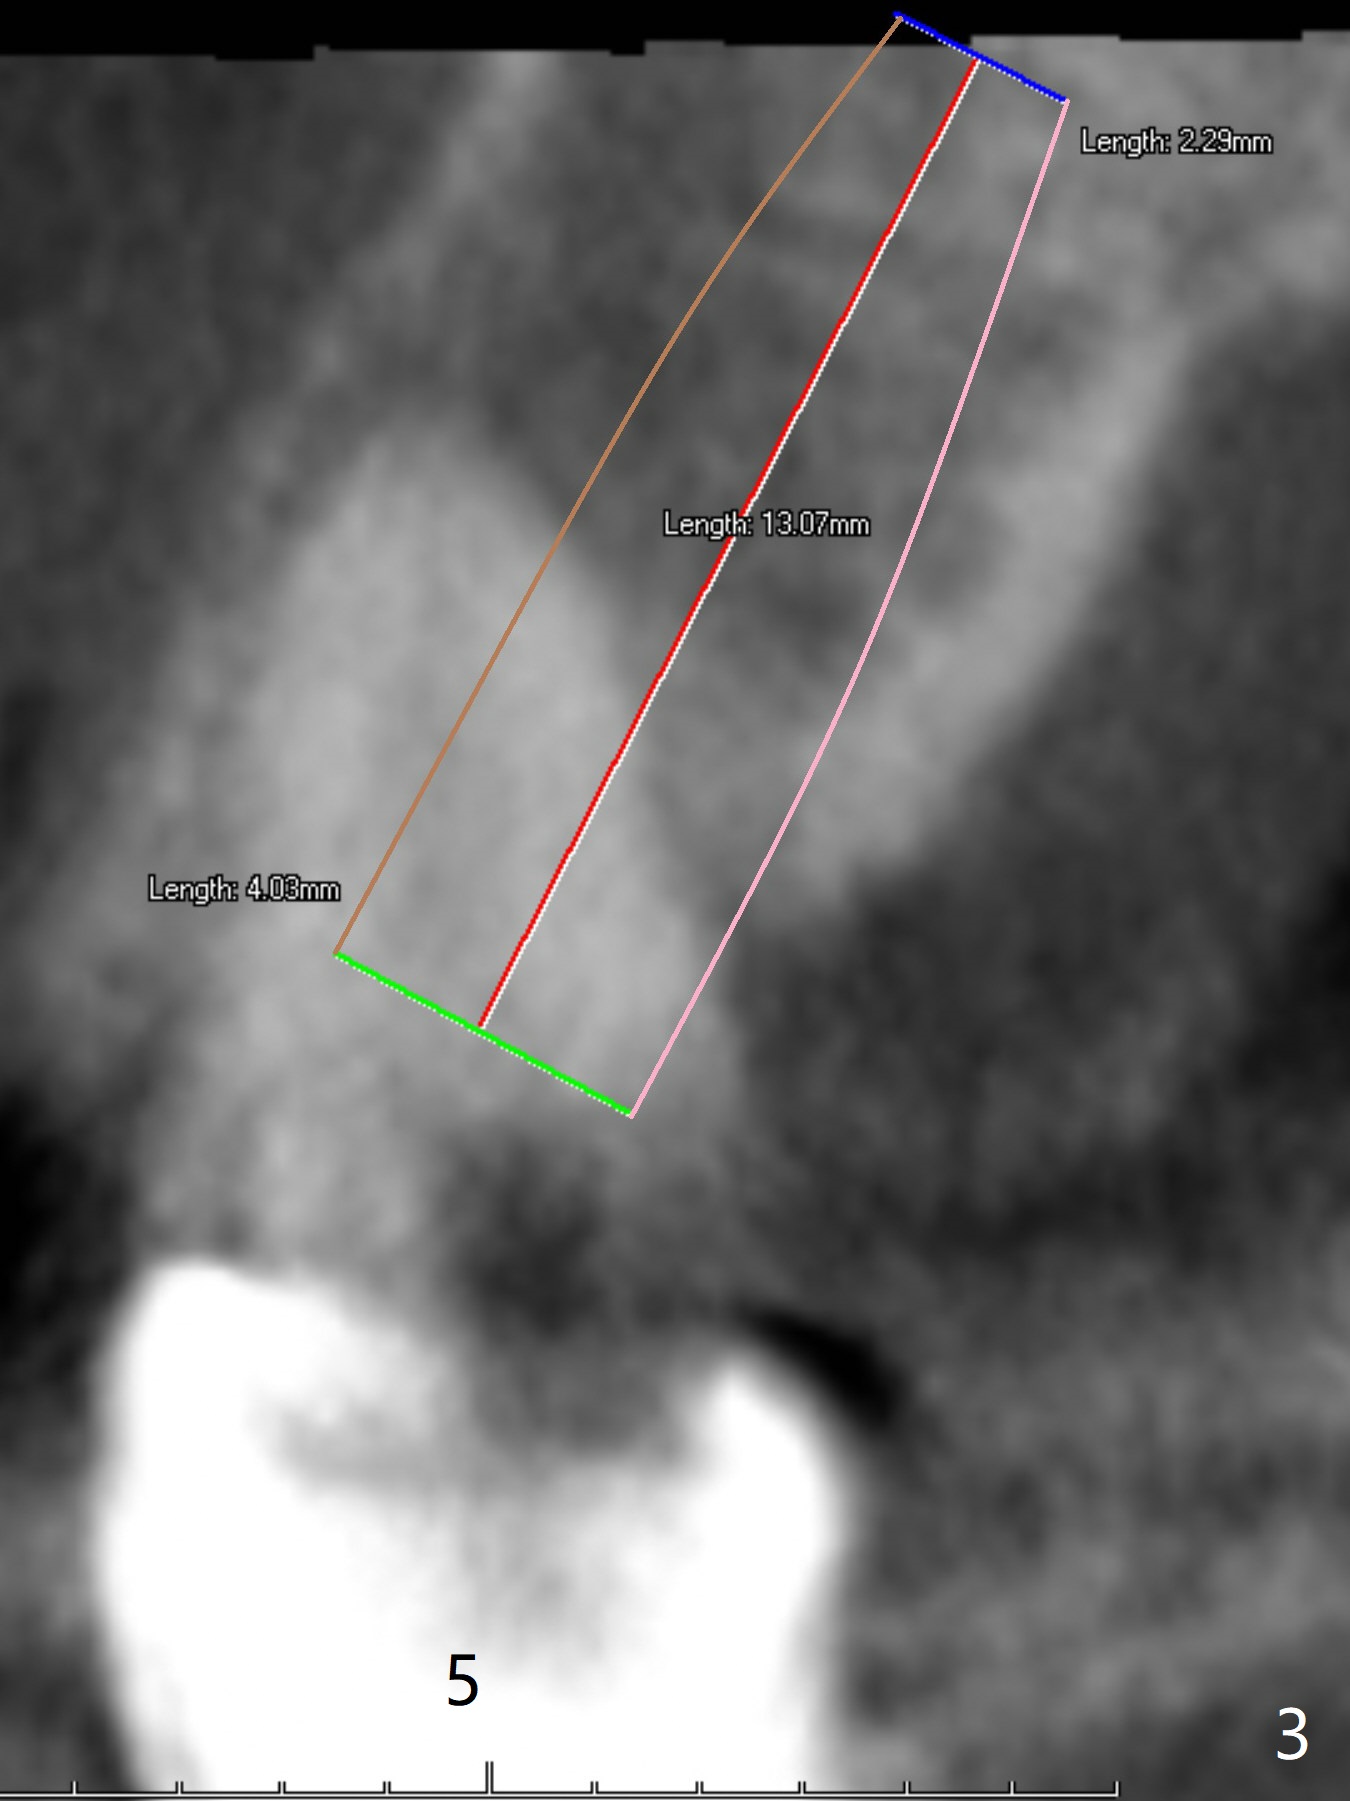

A 43-year-old woman has a failing upper right bridge (Fig.1: #2-5). While the abutment at #5 has apparently palatal open margin (Fig.2,3) and that at #4 has severe palatal bone loss (Fig.4 arrow), that at #2 has the poorest prognosis (Fig.6,7). Panoramic X-ray or PAs will be taken because of CBCT cone cut when the patient returns for #30 and 31 post-implant follow-up. Alginate impression will be taken for the upper right quadrant for provisional. The bridge will be sectioned between #3 and 5 (Fig.1 red lines) to determine salvageability of the abutments at # 4 and 5. If the latter are ok, the abutment at #2 will be extracted (expected to be loose) and implants will be placed at #2 and 3. If #4 is bad while #5 is ok, the former will be extracted and implants will be placed at #2 and 4 with a bridge. If #5 is bad while #4 is ok, implants will be placed at #2, 3 and 5.